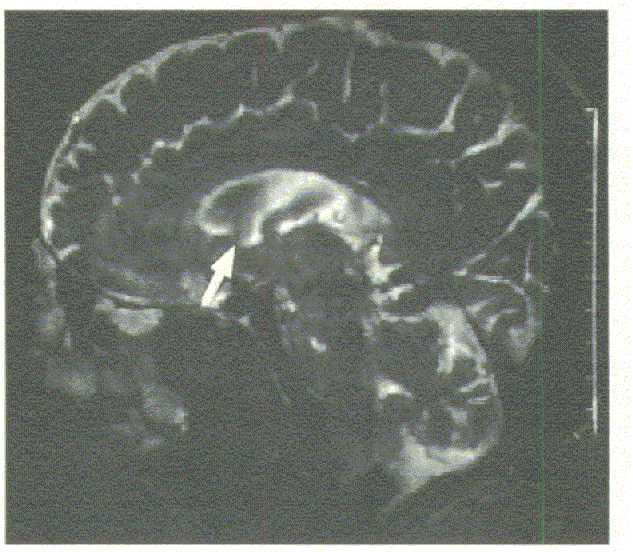

図11  T2強調画像によるMR-cisternography(NPH)